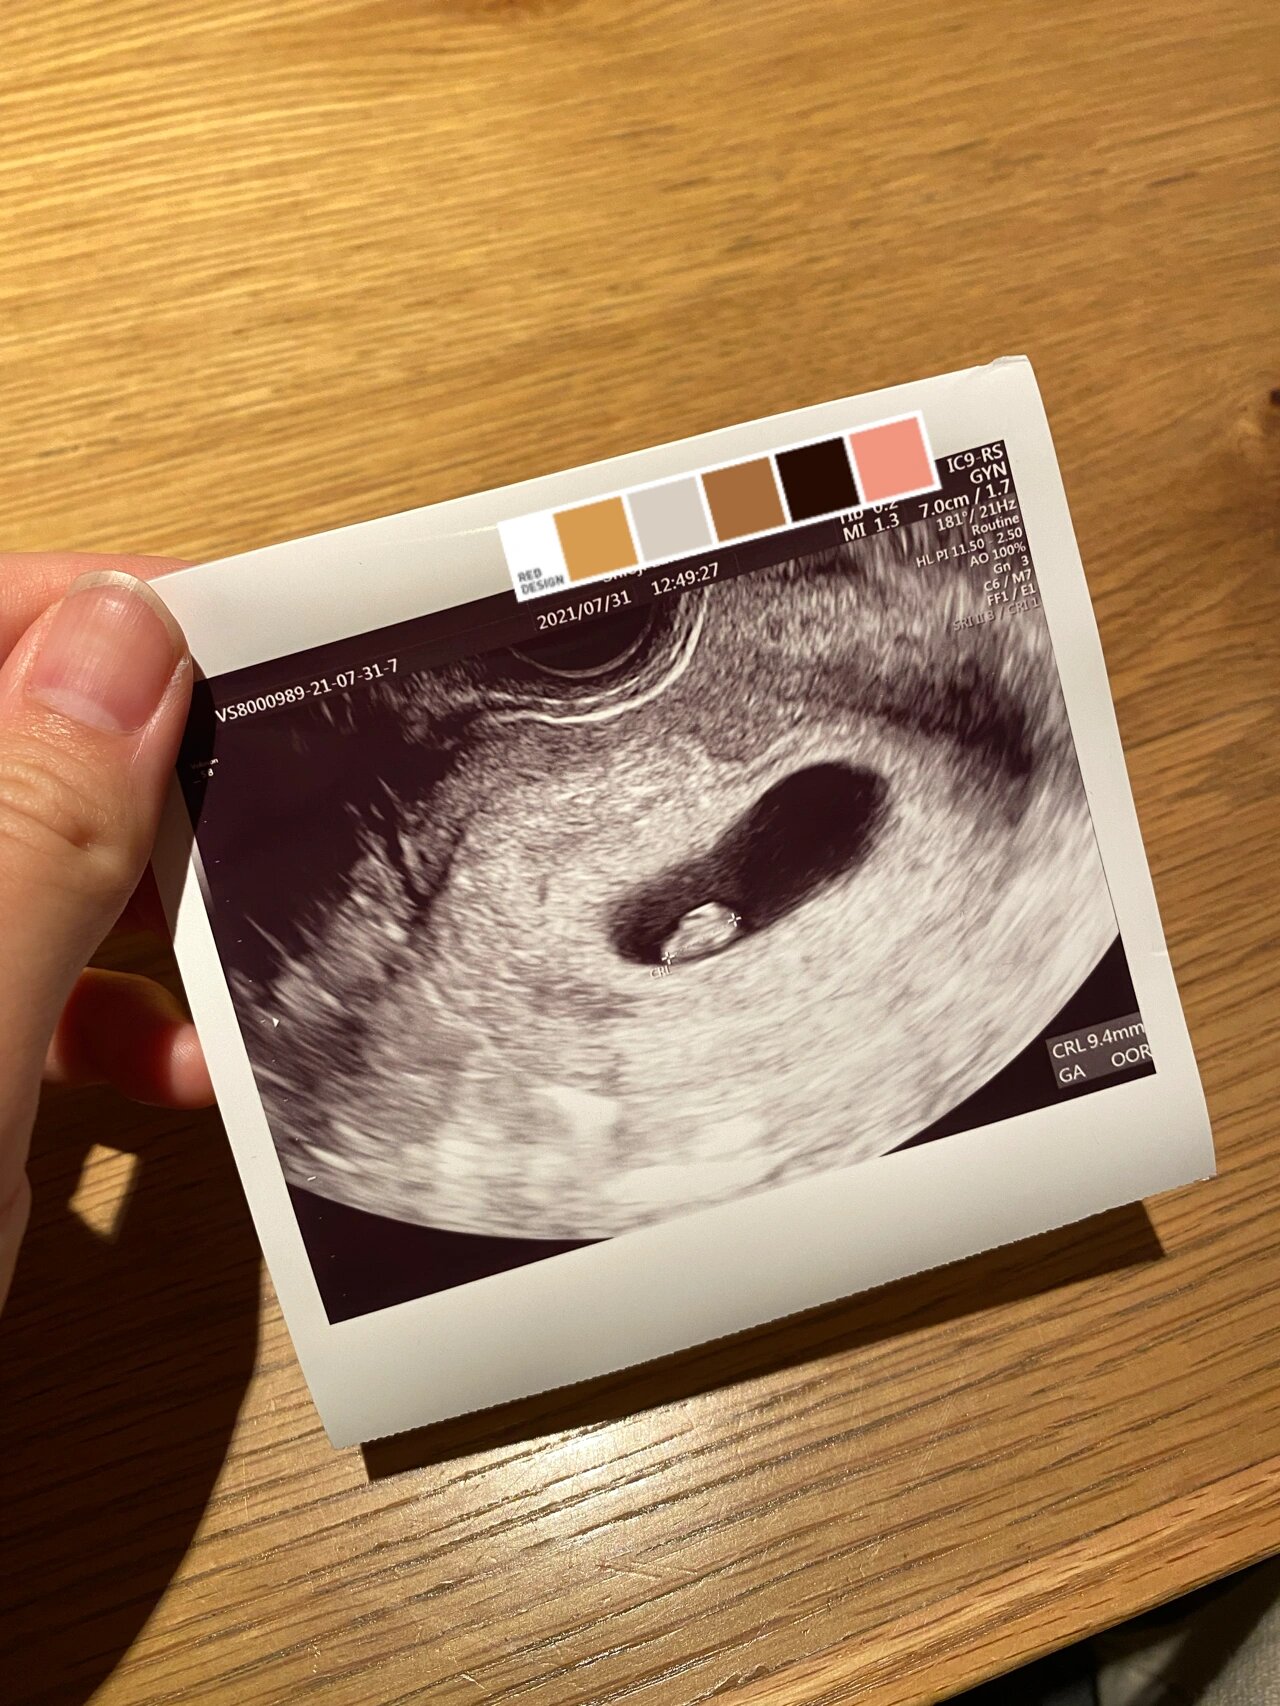

孕7周查了胎心胎芽

图片尺寸1136x1136